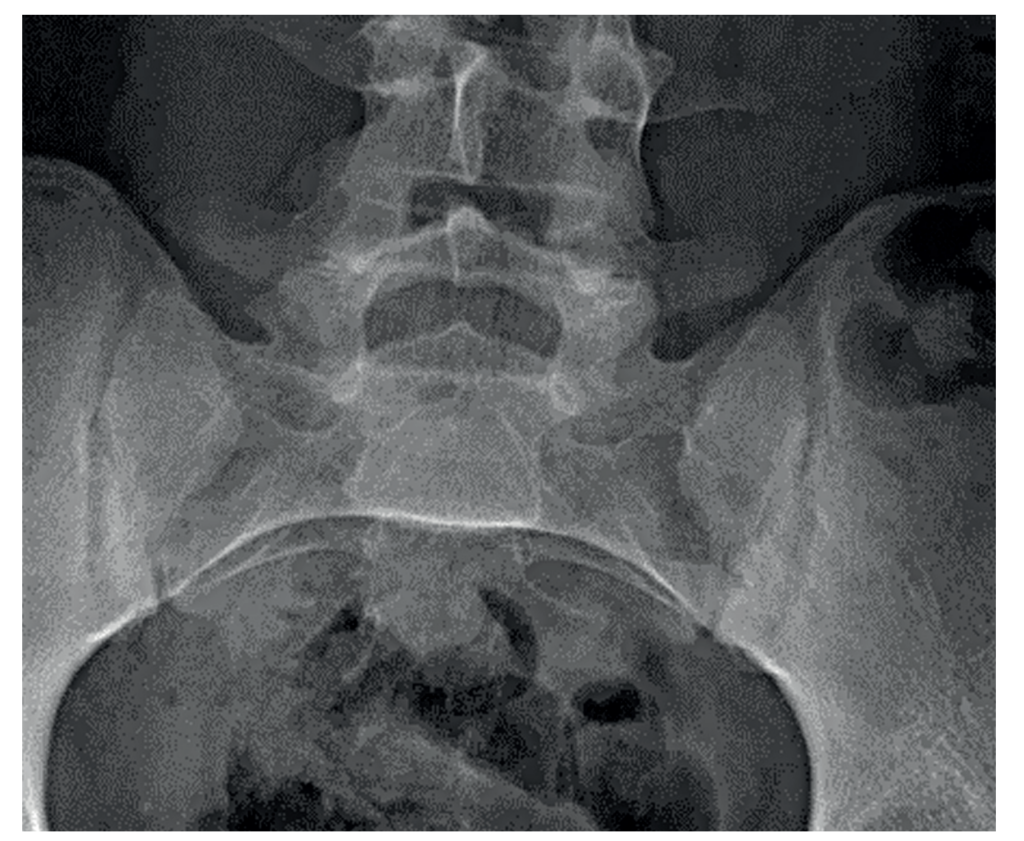

Recent investigations showed normal full blood count, renal and liver profile with a raised CRP of 10mg/L, and erythrocyte sedimentation rate (ESR) of 21mm/hr. HLA-B27 was positive. On a review of previous pelvic x-rays, radiographic progression can be seen between 2007 (Figure 1), showing SIJ joint widening, and 2015 (Figure 2), showing SIJ sclerosis and erosions, and 2023 showing bilateral SIJ fusion (Figure 3).

Figure 1: SIJ x-ray in 2007 showing SIJ widening and early changes of sacroiliitis | Figure 2: SIJ x-ray in 2015 showing bilateral sclerosis and erosions | Figure 3: SIJ x-ray in 2023 showing bilateral ankylosis